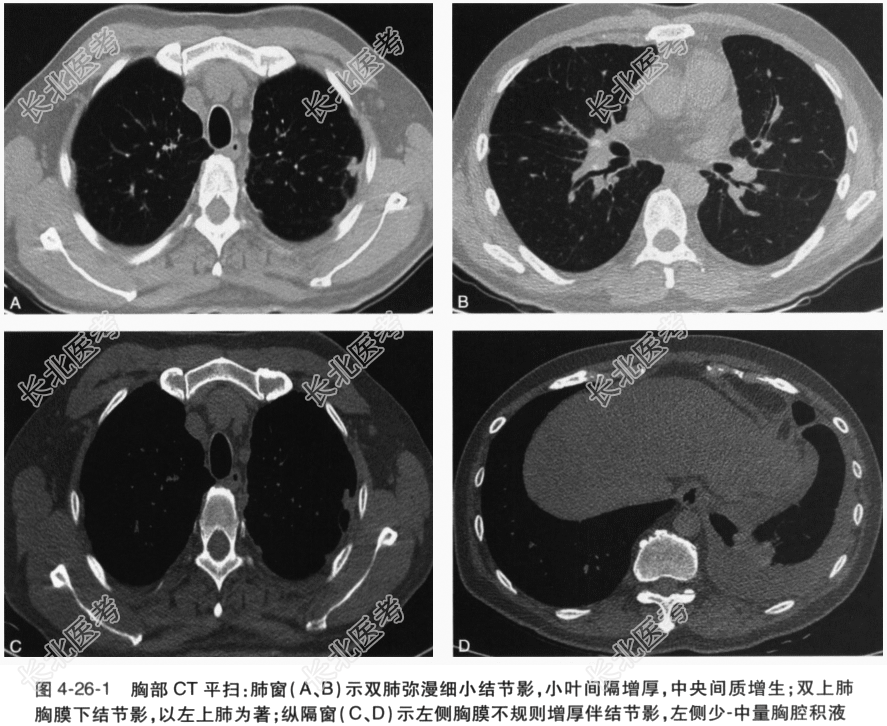

患者男性,52岁,银行职员。主因“胸腔积液2年余”。患者2年前体检发现左侧胸腔积液,多次就诊于当地及外省市三级医院,给予反复多次胸腔穿刺,胸腔积液查找脱落细胞及抗酸杆菌、肿瘤标志物、类风湿因子、细菌培养、T-SPOT和胸腔积液ADA检查均阴性,胸膜活检病理示慢性炎症。先后予以抗感染治疗、诊断性羟氯喹抗风湿免疫治疗及诊断性抗结核治疗,胸腔积液均无明显减少。为进一步明确诊断,收入我科。患病以来精神好,胃纳可,睡眠好,大小便正常,无明显体重下降。入院查体:T36.6℃,P89次/min,R15次/min,BP117/76mmHg。神清,步入病房,查体合作。全身皮肤无溃烂,浅表淋巴结无肿大。巩膜无黄染。口唇无发绀,咽喉不红,扁桃体不大。胸廓对称无畸形,胸骨无压痛;触觉语颤左侧减弱,未触及胸膜摩擦感;双肺叩诊呈清音,左下肺叩诊浊音,肩胛下角线左肺下界上移;右肺呼吸音清晰,左侧呼吸音减弱,未闻及胸膜摩擦音。心率89次/min,律齐;各瓣膜听诊区未闻及病理性杂音。腹软,全腹无压痛,无肌紧张及反跳痛,肝脾肋下未触及,肝肾区无叩击痛,肠鸣音3次/min。关节无红肿,无杵状指(趾),双下肢无水肿。肌力正常,肌张力正常,生理反射存在,病理反射未引出。既往史及个人史:冠心病史7年,心脏支架植入术后,未服用药物。关节肿痛及结膜炎反复发作。否认鼻炎、哮喘史。已婚已育1子。吸烟20余年,平均20支/d,已戒烟2年。否认冶游史。辅助检查:血常规、肝肾功能:均正常。NT-proBNP:正常。CRP、降钙素原:均正常。肿瘤标志物:均正常。真菌G试验、乳胶凝集试验:均正常。T-SPOT:阴性。心脏超声:左心收缩功能正常,左心舒张功能正常。EF:66%。胸部CT平扫(图4-26-1):双肺肺门及支气管血管束中央间质增生,小叶间隔增厚,双侧肺野弥漫性细小结节影;双侧胸膜局限性增厚及多发结节影;左侧少-中量胸腔积液;冠脉支架植入术后;心包少量积液。